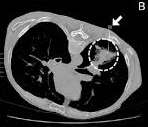

- Rx ingreso (7/11/2011): infiltrados perihiliares sin poder valorar derrame (Rx rotada, aunque asimétrica en

radiolucencia). Se solicita TC con la sospecha de Aspergilosis.

- TC tórax (8/11/2011): condensación alveolar de forma triangular en lóbulo inferior derecho (LID), GG y

engrosamiento septos interlobulares en LLSS (IC/infección). Derrame pleural bilateral, loculado en la derecha.